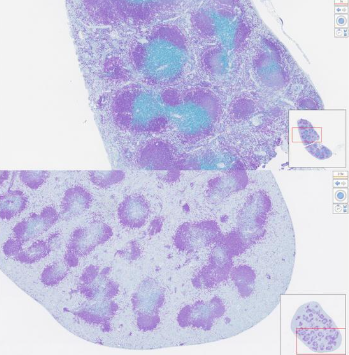

上图:未治疗小鼠脾脏中的蓝色染色B细胞。下图:用纳米颗粒处理小鼠脾脏中蓝色B细胞的减少。图片来源:约翰斯·霍普金斯大学医学院

该设计极为简化,仅包含3个核心组件,因此在未来的规模化生产和临床方面可能更具优势。动物实验中,纳米颗粒展现了强大的效力:将单剂纳米颗粒注射到健康小鼠体内24小时后,其循环血液中约95%的靶向B细胞被清除,脾脏中也有约一半的B细胞被破坏。